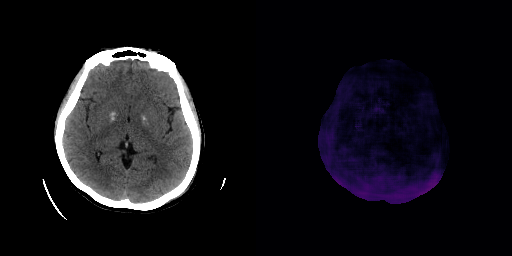

fig:qualitative_ich_ae

ICH

healthy